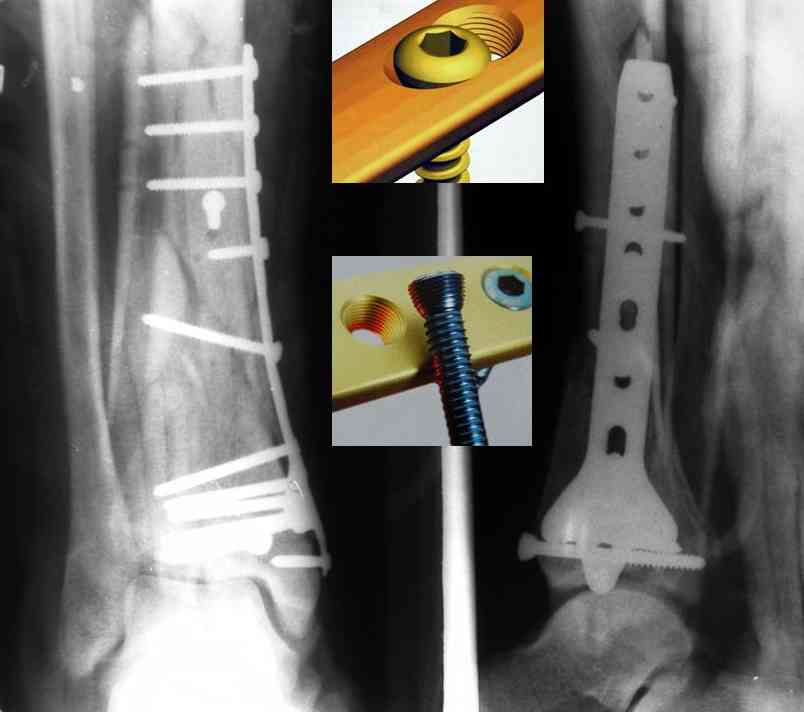

Кстати, при переломах переднего края по классификации АО В-3 при переломах пилона пластина укладывается по передней поверхности. Она достаточно тонкая и эластичная, не надо этого бояться. Посылаю три снимка.

На рентгенограммах типичный перелом пилона по типу С-3. есть опыт до 100 открытых опреаций у нас в клинике. 20 примерно в год. Принцип один -все внутрисуставные переломы нуждаются в открытой репозиции и внутренней стабильной фиксации. При поступлении КТ не надо, так как получается только нагромождение костей. Истинной картины нет. Главное восстановить длину малоберцовой кости - это ключ к успеху. При поступлении меньше всего надо думать о сосудистых расстройствах, т.к. сама операция и репозиция даже сначала частичная даёт улучшение сосудитых нарушений. Причём очень быстро. Операция в 2этапа. При поступлении доступ позади наружной лодыжки, причём обязательно. После этого репозиция малоберцовой кости и фиксация пластиной 1/3 трубки под винт 3,5. Дренаж и любой аппарат наружной фиксации. Затем после спадения отёка на 5-7-10 день аппрат снимается и дугообразный разрез спереди от медиальной лодыжки 10-12 см. Главной чтобы расстояние между 1 и вторым разрезом было не меньше 7-8 см. Тогда не будет некрозов лоскутов. Таранная кость используется как матрица на неё укладываются отломки и фиксируются пицами. Ренг-контроль. Отломки лежат все отдельно, но ничего не высыпется. При переломах С-3 всегда нужна костная пластика (из крыла). Фиксация пластиной лист клевера простой или LCP. Гипс не нужен. Дренаж до 48 часов. Операция длится 3-4 часа обязательно без жгута. Посылаю примерно такой же случай.